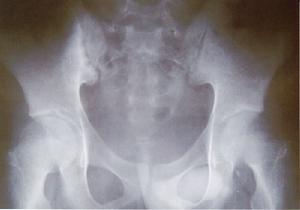

X線正位片顯兩髂後上棘高低不等,斜位片可見骶髂關節間隙加寬,凸凹關係紊亂。